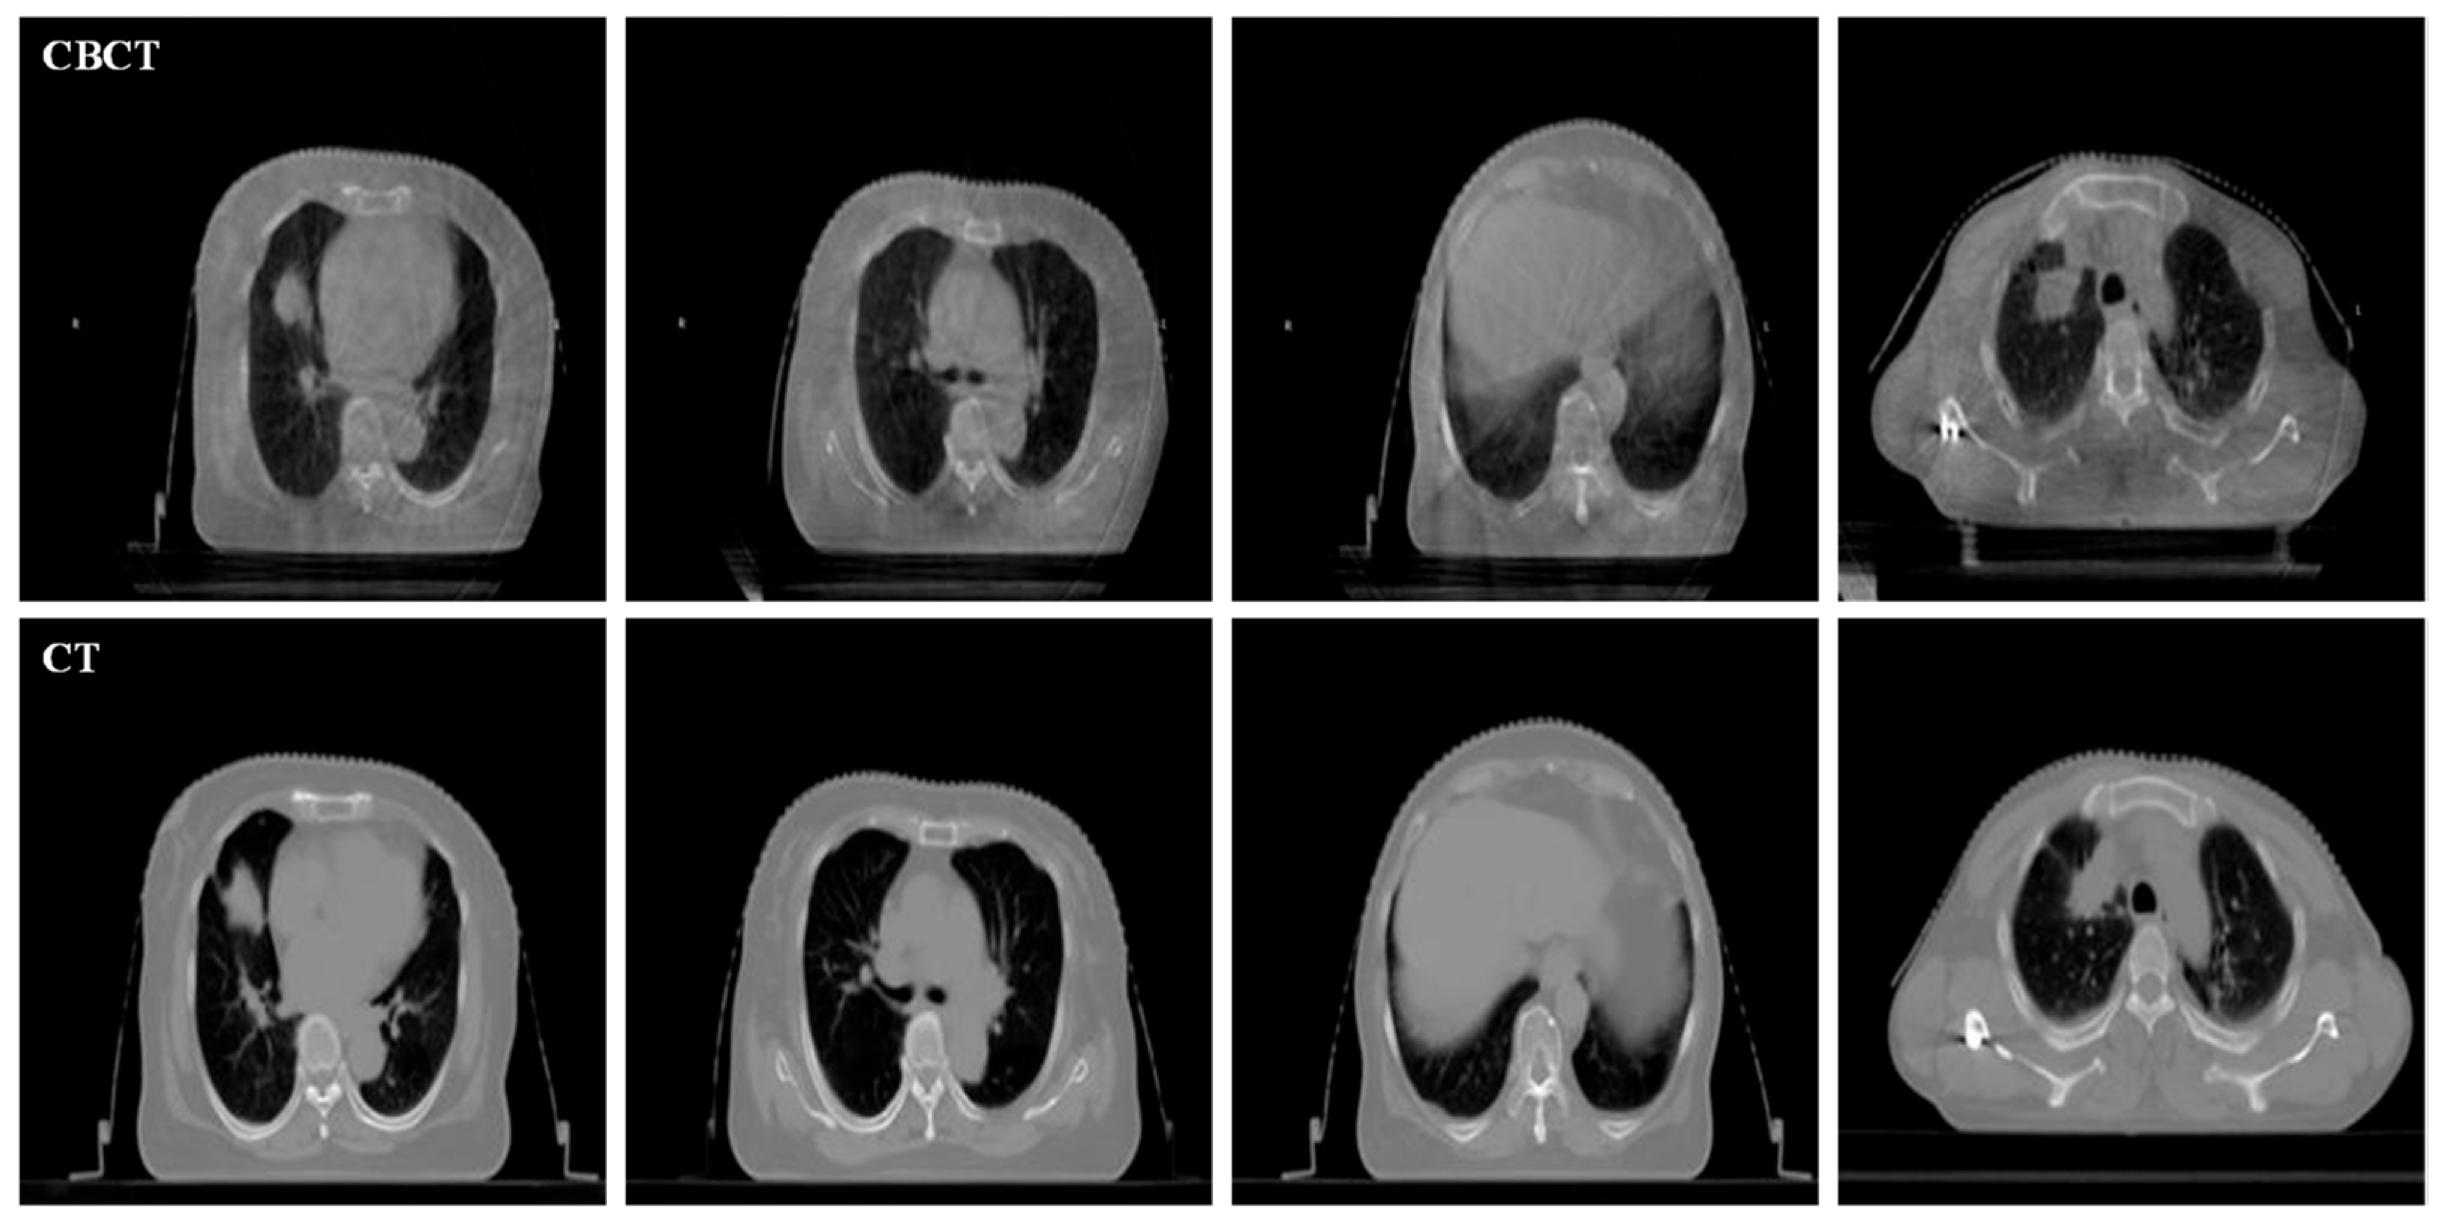

The experimental data are shown in Figure 6, and all of them are acquired from the Affiliated Hospital of Yunnan University, decrypted, and anonymized. Both CBCT and CT images are acquired for each sample of the same patient. The CBCT images were obtained by linac (XVI, Elekta Solutions AB, Stockholm, Sweden), and the corresponding CT images were acquired by Philips Brilliance Big Bore CT equipment, with a slice thickness of 3 mm. All images in our experiment were resized to 256 × 256 pixels. For this work, we have acquired CBCT and CT image sequences of three patients, totaling 120 pairs of images. Since there is little difference between the different sequence images of the same patient, four sections with large differences were selected as experimental data for analysis.

Figure 6.

Experimental data. The first line is CBCT and the second line is the corresponding CT.